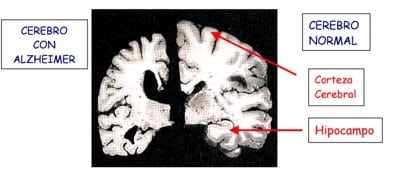

• En personas que sufren de la enfermedad de Alzheimer, las células mueren inicialmente en partes clave del cerebro:

• La corteza cerebral (sustancia gris), el hipocampo y el núcleo basal de Meynert.

Cada hemisferio del cerebro está dividido en cuatro lóbulos:

- Frontal

- Parietal

- Temporal

- De ellos, el más trastornado es el temporal, y es precisamente este lóbulo quien controla muchas funciones importantes, incluyendo el lenguaje, la memoria, las emociones, la concentración y el sentido del tiempo y la individualidad